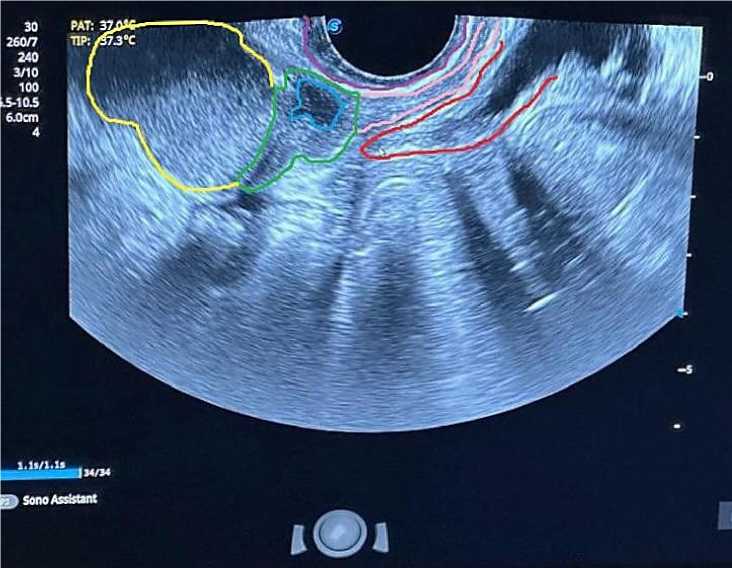

Рисунок 1. Трансвагинальное исследование. Поперечное сканирование (Желтая линия – опухоль шейки матки; Розовая линия – влагалище; Темно-синияя линия инвазия; Горчичная линия – опухолевая инфильтрация; Зеленая линия - опухолевая инфильтрация верхней трети влагалища)